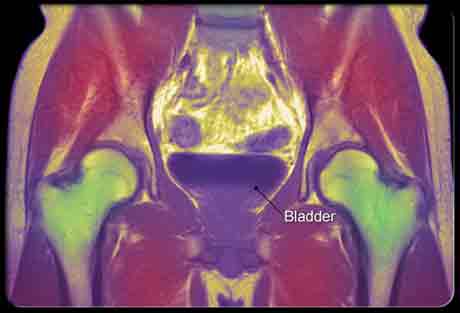

Есть несколько тестов, которые помогают определить причину недержания мочи. Ультразвуковое изображение может показать, как мочевой пузырь и мочеиспускательный канал изменяются, когда вы мочитесь или кашляете. Тест с прокладкой показывает, сколько мочи непроизвольно вытекает в течение дня. Нагрузочное испытание мочевого пузыря помогает проверить наличие стрессового недержания. Цистометрия измеряет давление пузыря и может помочь диагностировать неотложное недержание мочи. МРТ сканирование (магнитно-резонансная томография) может показать проблемы, которые не могут быть замечены другими тестами.